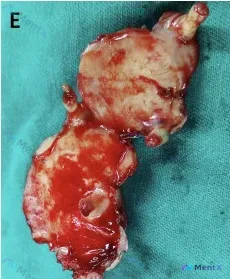

看到一个结合HAC皮瓣手术史的大体标本资料,整理一下思路。 病例与标本背景 - 临床背景:HAC皮瓣手术,术中暴露了腹侧区域及根部的病灶。 - 大体标本描述: - 形态:分叶状/多结节状,切开标本,切面暴露完整; - 颜色:显著异质性,以灰白色、黄白色实性组织为主,伴大面积鲜红色出血区; - 质地:...